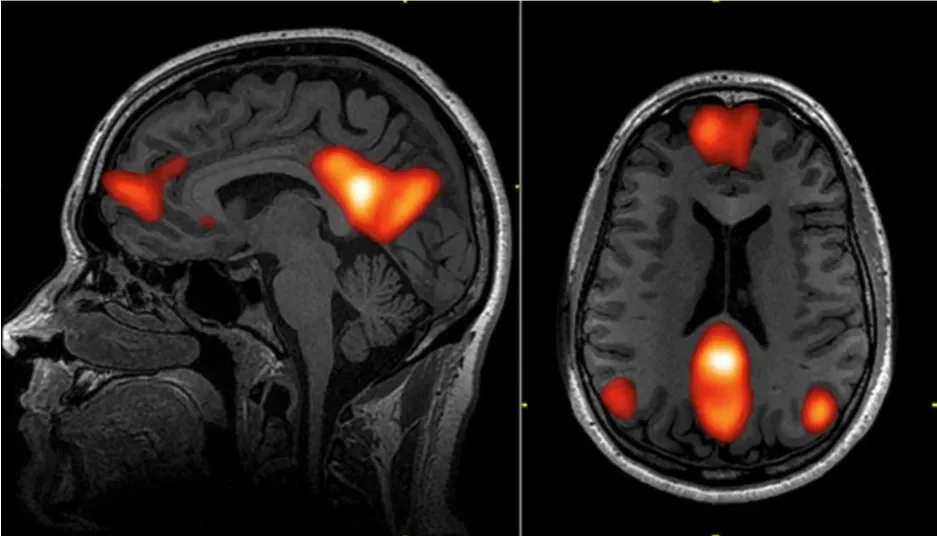

Functional MRI scans showing regions of the default mode network: dorsal medial prefrontal cortex, posterior cingulate cortex, precuneus, and angular gyrus. Source: http://www.frontiersin.org/Neurotrauma/10.3389/fneur.2013.00016/full

Anxiety disorders are increasing across all demographics in the U.S., and given the extensive side effect profiles of conventional pharmaceuticals, many of us are searching for alternative treatment modalities. Relatively more recent neuroimaging studies and clinical research have provided compelling evidence that targeting the brain’s Default Mode Network (DMN) with psychedelic therapies could play an integral role in a multimodal approach to alleviating anxiety symptoms.

The DMN is a network of interconnected brain regions that becomes active when we’re engaged in self-referential thought processes, introspection, and not focused on the external environment. You can think of it as being focused inward on the “self” vs. outwardly engaged with the world. This is not, in and of itself, a pathologic state. Introspection is quite evolutionarily beneficial for humans because it enables self-reflection that enhances decision-making, fosters social cooperation, and promotes adaptive learning for survival. This adaptive trait can become maladaptive, however, when the DMN becomes overactive relative to other neural networks. An overactive DMN is associated with the repetitive negative thinking, rumination, and unease that is characteristic of anxiety states.